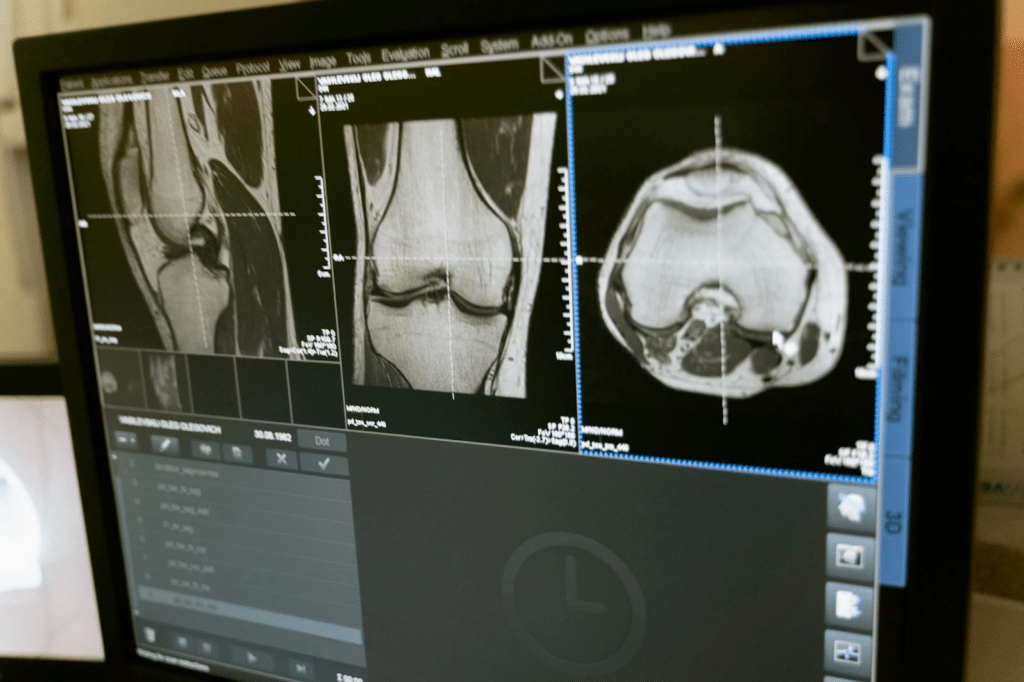

Resonancia Magnética (RM) de alta resolución

La resonancia magnética, basada en campos magnéticos y ondas de radio, ha evolucionado con la incorporación de imanes más potentes y secuencias de imágenes avanzadas. La RM de alta resolución permite visualizar detalles anatómicos con una claridad sin precedentes, siendo especialmente útil en la neuroimagenología y la evaluación de tejidos blandos.